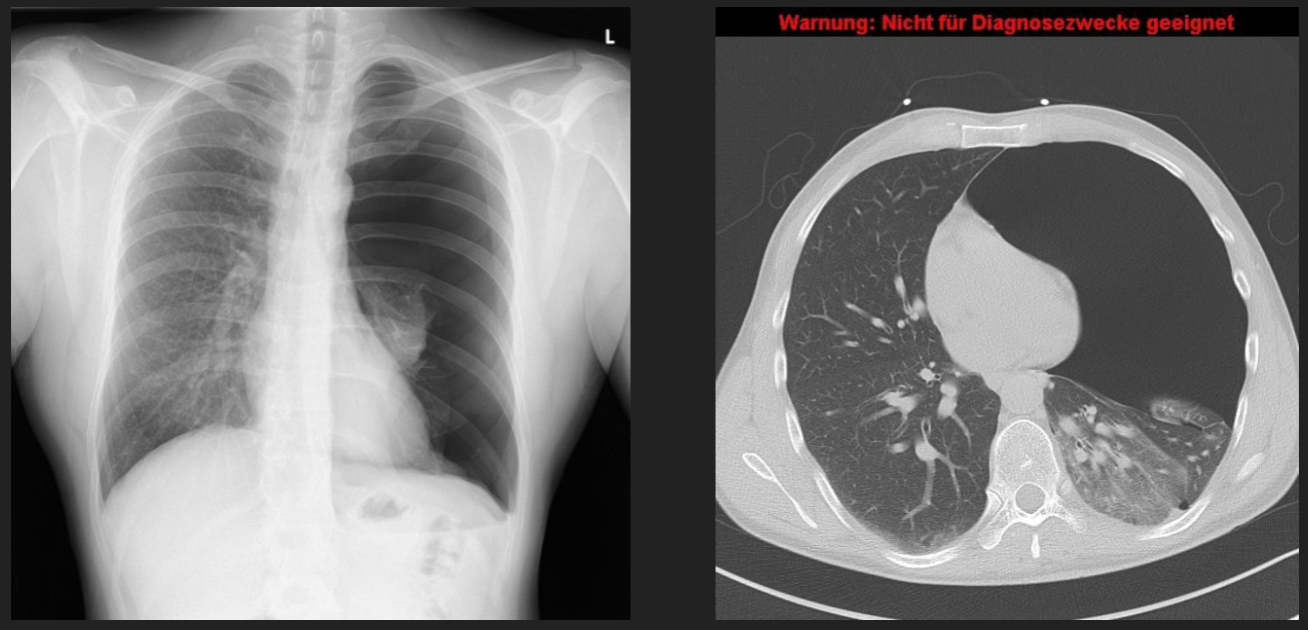

tension pneumothorax